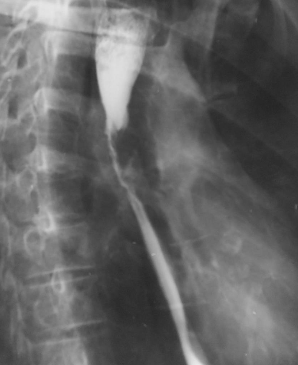

Diverticul medioesofagian complicat cu fistulă

Diverticul medioesofagian complicat cu fistulă esobronșică